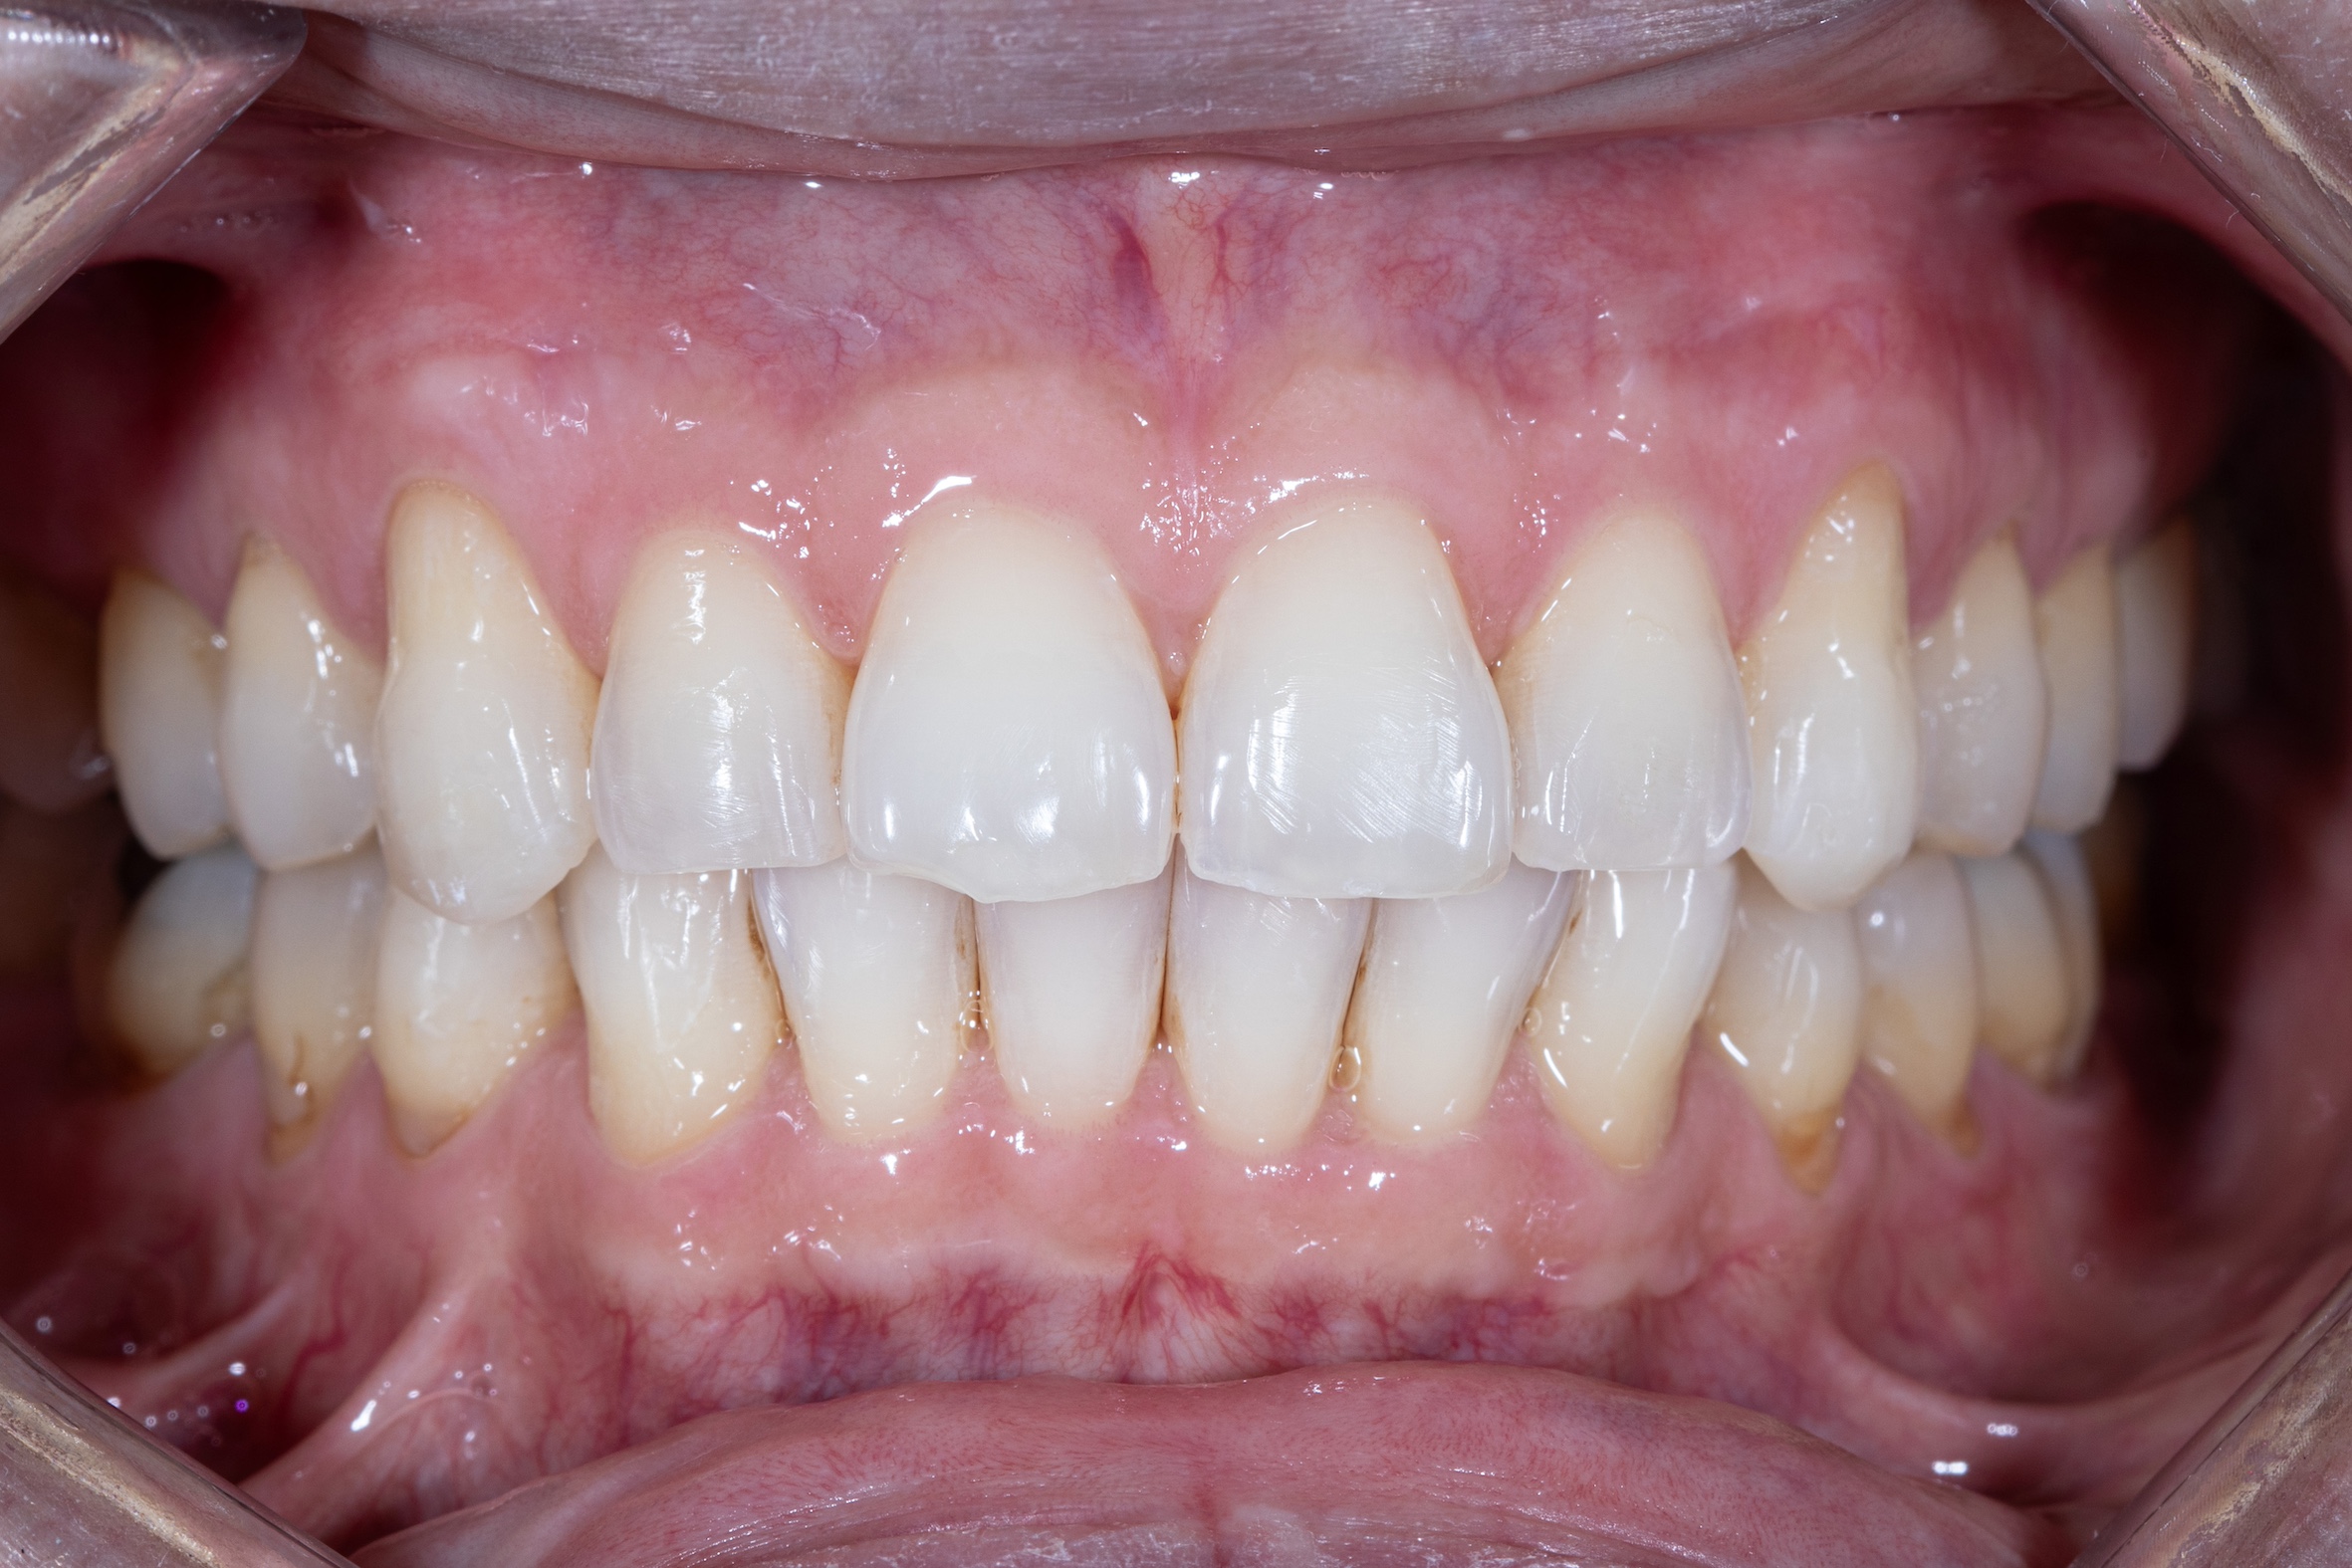

Before